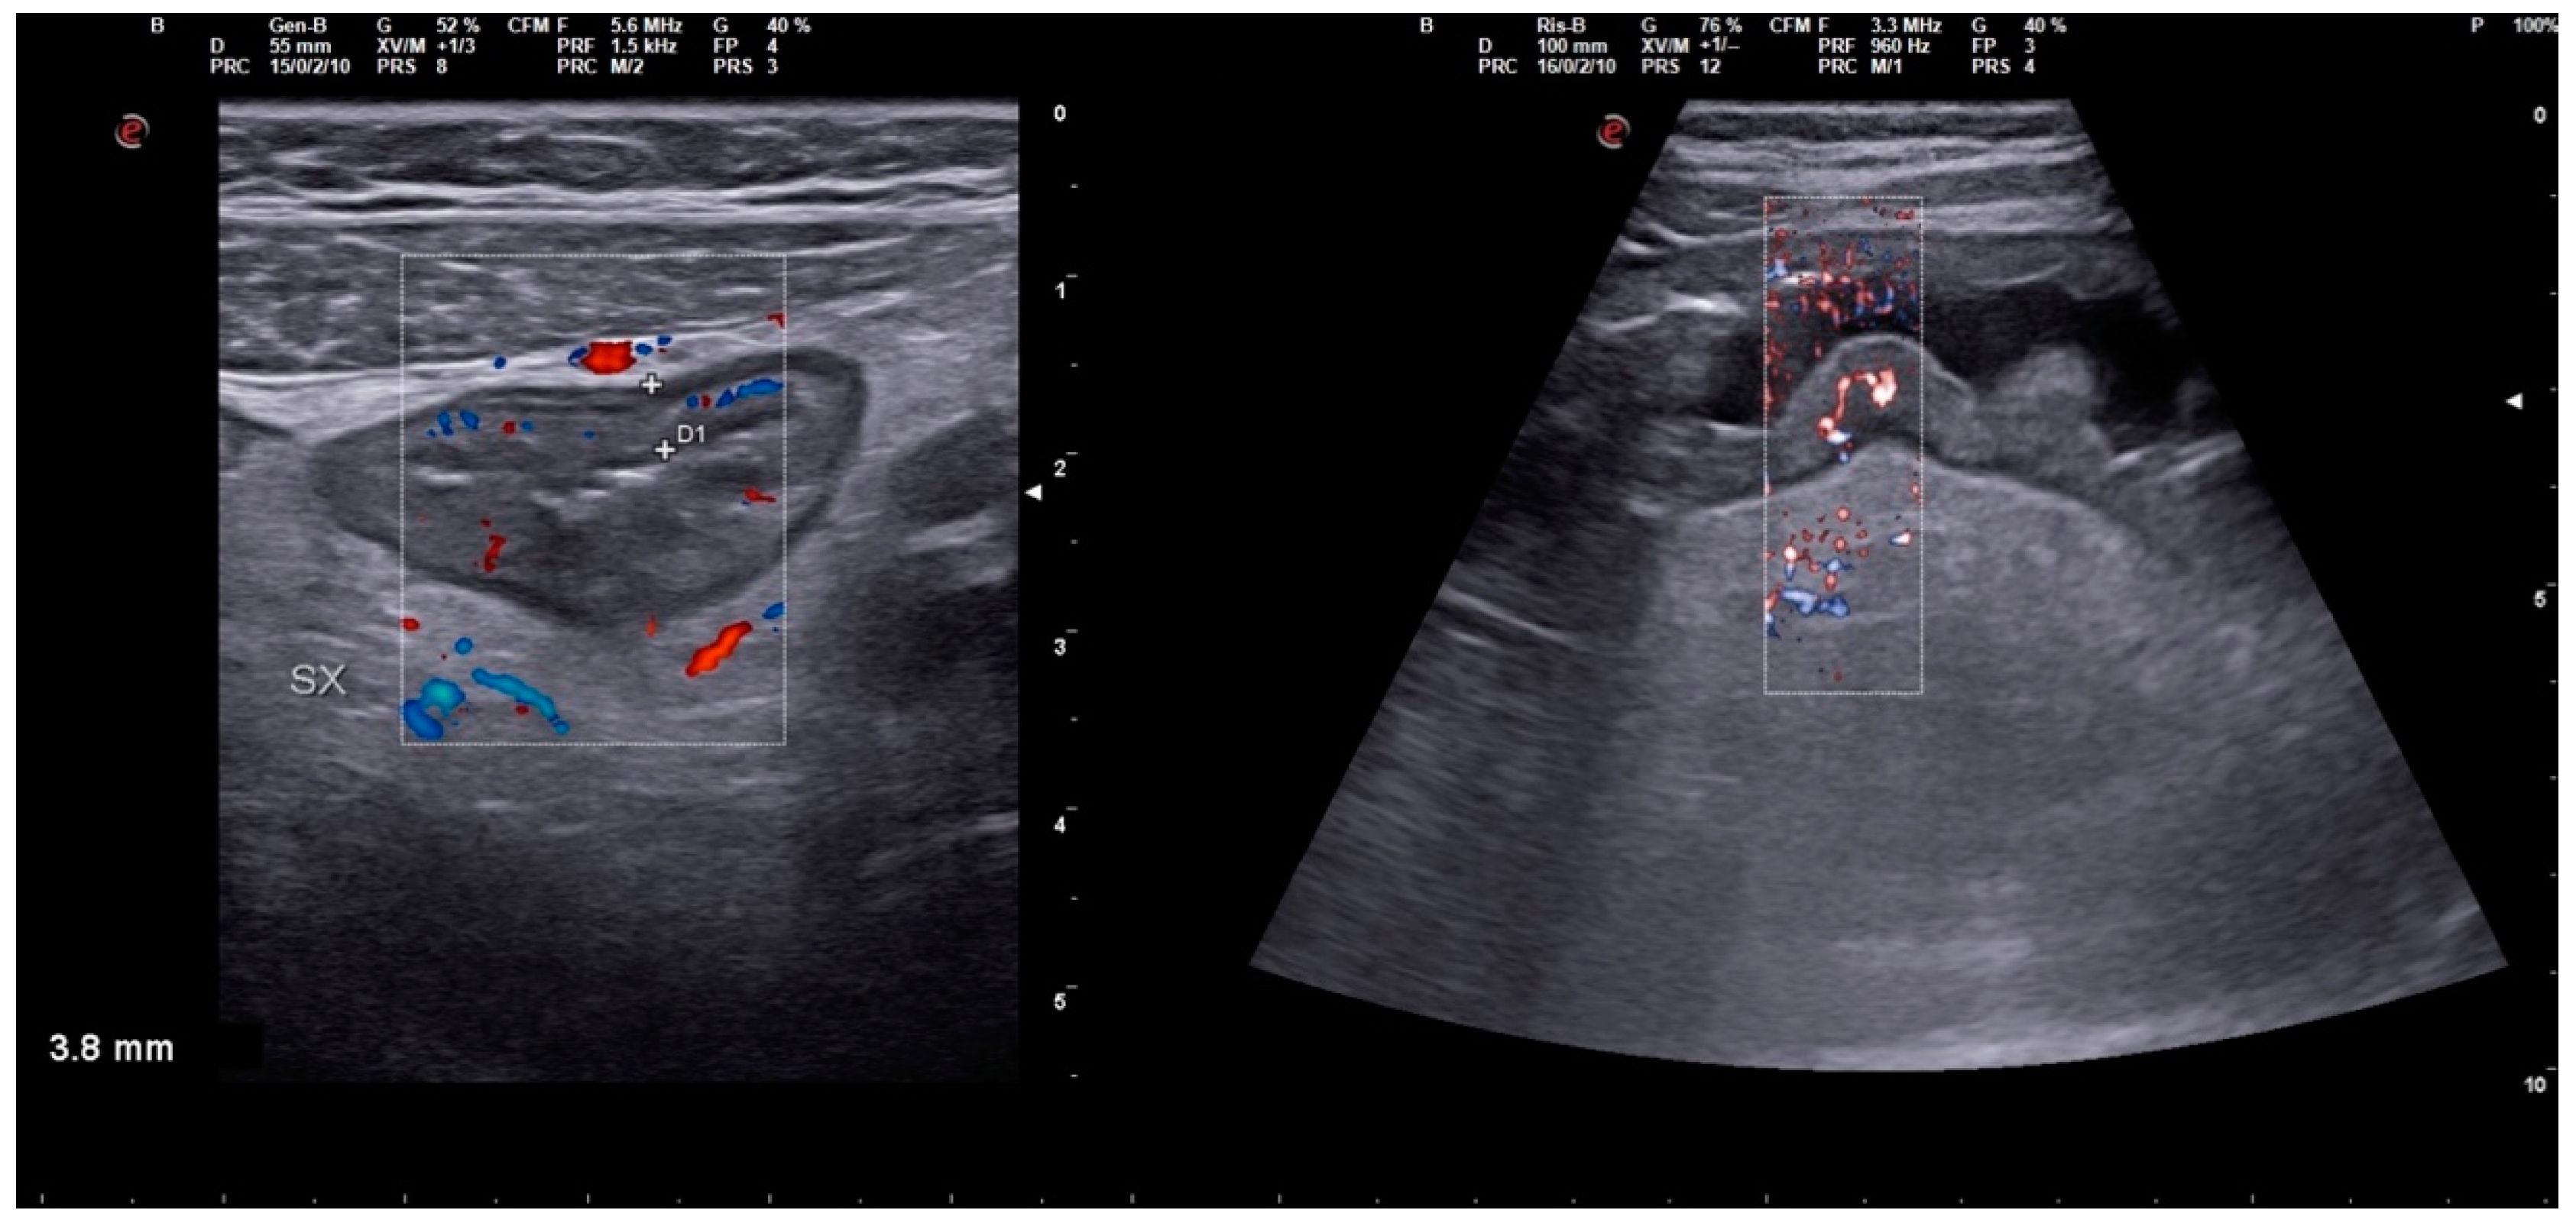

2. Case Description